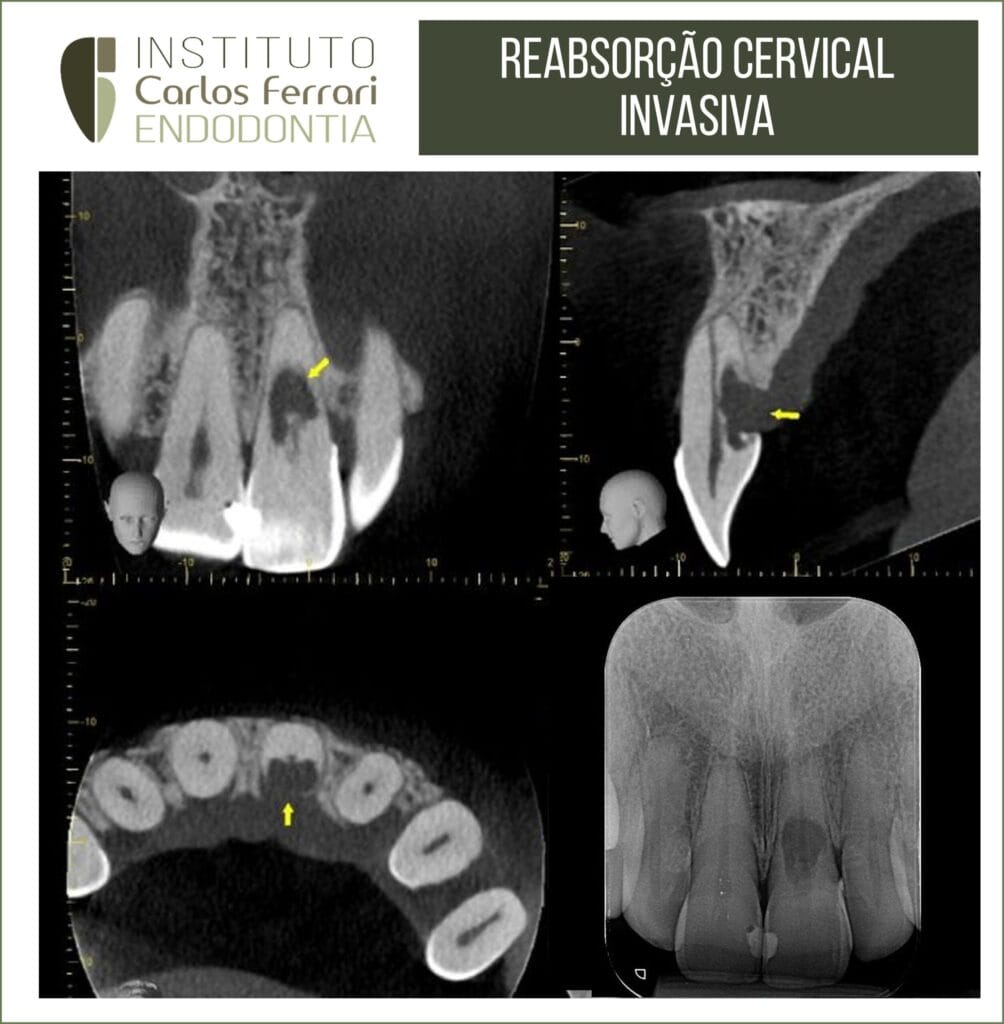

Reabsorção radicular cervical externa. Paciente 30 anos, sexo feminino, com diagnóstico de reabsorção radicular cervical invasiva, após queixa de dor na região gengival palatina. Na primeira sessão foi realizada a descontaminação do espaço endodôntico e medicação com Bio C Temp (Angelus).

Retratamento em dente com reabsorção externa